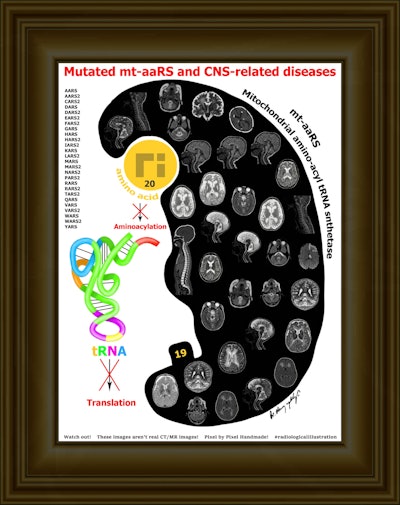

Conceptually, I think it is possible to define the term “radiological illustration” as an emerging discipline that transforms medical imaging data into an aesthetic and didactic narrative. I emphasize that with the motto “pixel by pixel handmade.” I am trying to open a “new path” for the use of visual communication in medical education by trying to combine scientific accuracy in radiological terms with artistic creativity. With this statement, I am trying to express that instead of modifying radiological images, I draw each pixel by hand using technological tools and create a new visual that is both artistically and scientifically original, while remaining faithful to radiological principles.

It’s important to note that radiological illustration should not be confused with medical illustration. The former has yet to be systematically defined in the literature. I believe it deserves recognition as a distinct sub-branch within the broader medical illustration domain.

In September 2025, I had the honor of exhibiting 35 selected illustrations at an international neuroradiology congress in Istanbul, jointly organized by the European Society of Neuroradiology, the American Society of Neuroradiology, and the Turkish Society of Neuroradiology. There were over 1,500 attendees. For the first time, my illustrations were displayed as true works of art under gallery lights and among a crowd. It was an unforgettable experience that left me with deep emotional memories.